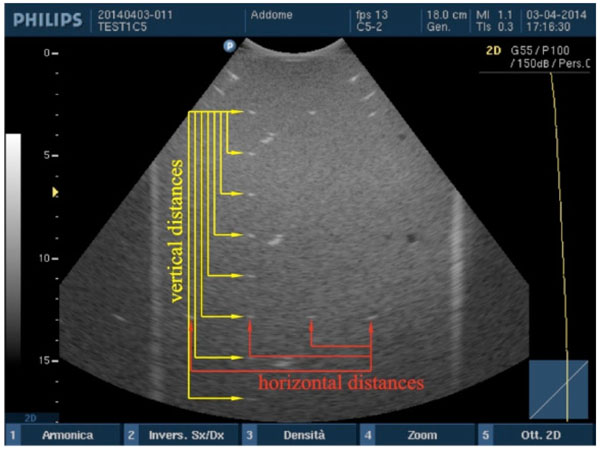

Accuracy in distance measurements. For each pair of point targets the measurement distance relative error between the nominal and the measured distance in the ultrasound image is calculated for both horizontal and vertical distances.

Vertical and horizontal distances are measured “from peak to peak” of the wires sections within the two phantoms and compared with their nominal values by an in-house software [3]: in particular, after the ultrasound image is processed in a workstation, first, the scale factor is automatically calculated from FoV then the operator is asked to choose n test object pairs by clicking on the image without care about centering each target because their barycentric coordinates are automatically calculated within a Region of Interest (ROI). These latter are then used for measuring the distance between each pair of wires, so errors due to operator subjectivity can be neglected. Therefore, the measurement distance relative error ek=|srk−smk|/srk×100 between the nominal (srk) and the measured distance (smk) in the image is calculated for each pair (k=1, 2, ...n) along both horizontal and vertical distances [3, 11]. For the k-th distance and for each test, the accuracy in distance measurements is calculated by averaging relative error values ek over the images of the same group Fig. (3).